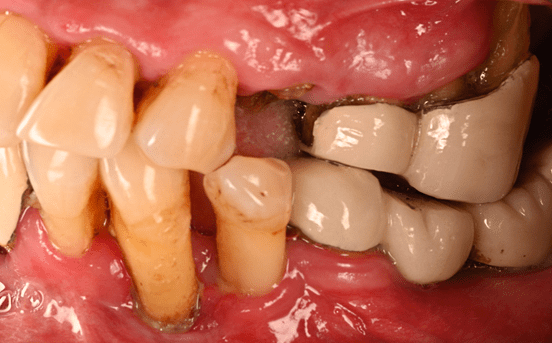

1. Type 2 treatment planning session – sectioning of bridges lower right, left and section of splinted crowns #3/4

2. Extraction: #3, 12, 13, 14, 17, 20, 21, 29

3. Allowing tissue to heal after bridge removal, open flap debridement of #4-11, the patient is aware that these teeth may fail and need a full maxillary denture